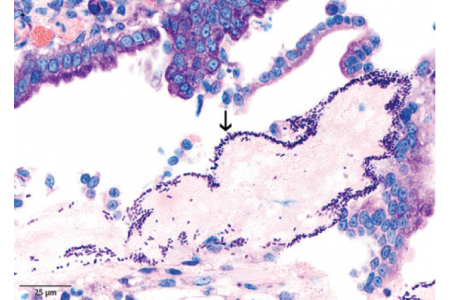

The results of this study demonstrate an apparent association between C. perfringens and the occurrence of acute haemorrhagic diarrhoea. The term “HGE,” which implies the involvement of the...